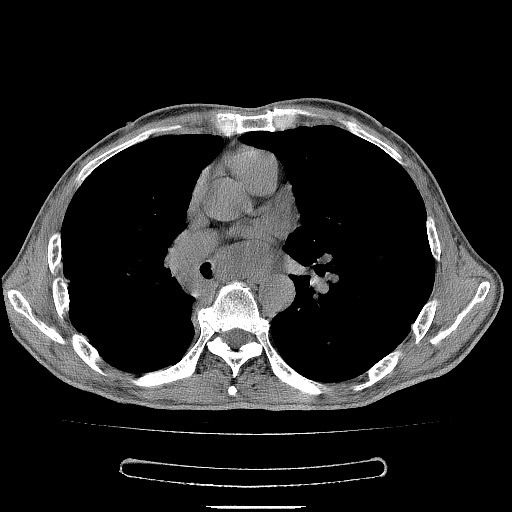

男性患者,63岁。右侧胸背部疼痛2月,加重一周。

考虑:右肺中央型肺癌并右肺下叶不张;两肺尖继发性肺结核。

还有纵隔多处肿大淋巴结及肋骨的改变、两肺多发结节灶。

右下中央型肺癌伴肺内纵膈转移。

右下肺中心型肺癌并肺不张

纵隔淋巴结转移

考虑右中心型肺癌并右下肺不张,肺及纵隔,左肋骨转移。

右肺下叶支气管狭窄闭塞,右下肺不张,气管前间隙淋巴结肿大,两上肺散在分部粟粒灶,沿肺血管支气管束分部,血管支气管束走形较为光滑。考虑右肺中心型肺癌合并肺不张,纵隔淋巴结转移,两上肺癌性淋巴管炎

右肺下叶中心性肺癌并纵隔淋巴结转移,左侧肋骨转移。双肺上叶继发性结核表现。

1)右肺下叶中心性肺癌并纵隔淋巴结转移,两肺转移,左侧肋骨转移。2)双肺上叶继发性结核。

右肺下叶中心性肺癌并纵隔淋巴结及两肺、左侧肋骨转移。双肺上叶继发性结核表现。